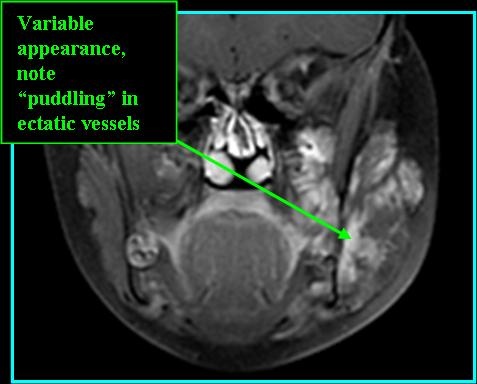

- MR:

- T2: high signal with differing apprearance based on vein diameter, phleboliths appear as dropped signal

- T1 post-contrast MR: highly variable signal - hypo- to hyperintense, homogenous or heterogeneous signal